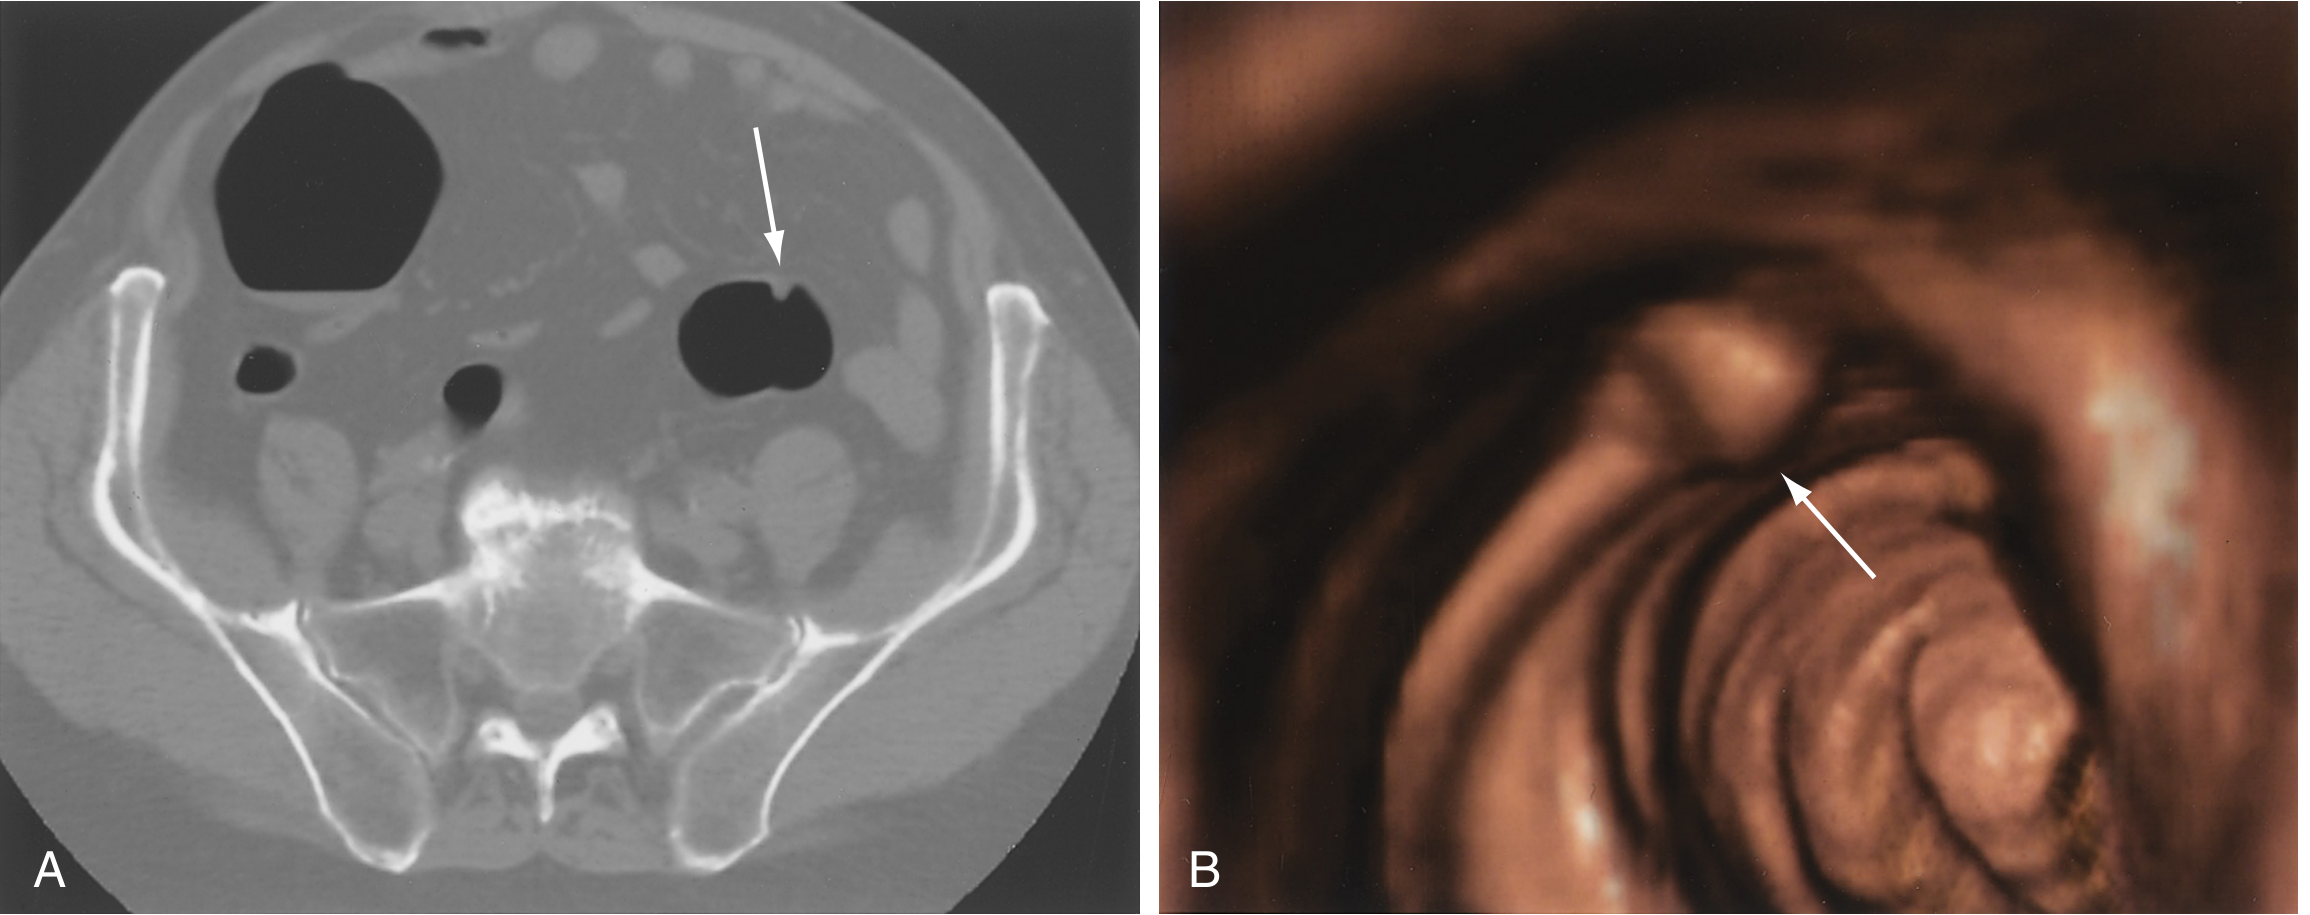

CT colonography showing sigmoid polyp on axial CT and 3D reconstruction

CT colonography: an 8-mm sigmoid polyp on axial 2D CT (A) and 3D endoluminal reconstruction (B) — Sleisenger & Fordtran's GI and Liver Disease

Sessile colonic lesion at colonoscopy and CT colonography

A 2-cm sessile colonic lesion (arrows): seen at colonoscopy (A) and on 3D CT colonography reconstruction (B) — Sleisenger & Fordtran's